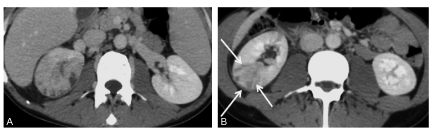

- sur le parenchyme rénal : une plage segmentaire hypodense de la néphrographie au temps tubulaire, le plus souvent triangulaire à base externe et à sommet caliciel, associée à des striations linéaires adjacentes ou sur d’autres secteurs du rein (pyélonéphrite multifocale) (figure 26.1) ;

Fig. 26.1. Pyélonéphrite aiguë multifocale. Scanner après injection de produit de contraste iodé au temps tubulaire.

Pyélonéphrite aiguë multifocale du rein droit se présentant sous la forme de zones d’hypodensité segmentaires triangulaires de la néphrographie (flèches).

Source : CERF, CNEBMN, 2022.